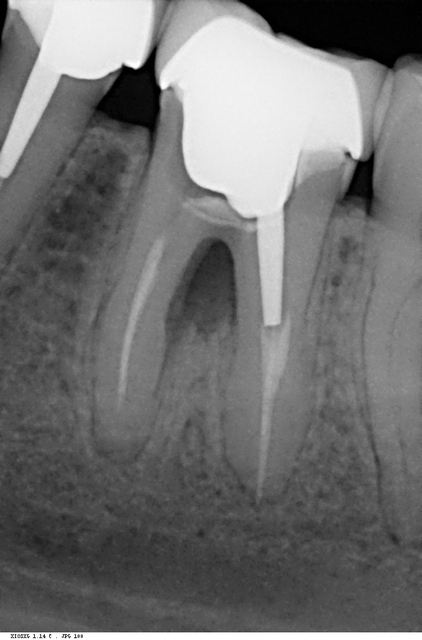

Parfois, c’est lors du forage d’un logement pour pivot que la fausse route se produit.

La perforation du plancher pulpaire peut être assimilée à une fausse route, elle peut être spontanée suite à une carie profonde ou accidentelle lors de traitements endodontiques ou de forages de logements de pivots.

Le diagnostic est facile à faire: les perforations saignent énormément et il faut systématiquement y penser devant une hémorragie endopulpaire. La radio avec des sondes radio opaques en place confirme généralement la perforation.

Le traitement le plus simple et le plus évident est l’obturation étanche de la perforation, en évitant soigneusement les dépassements intempestifs.